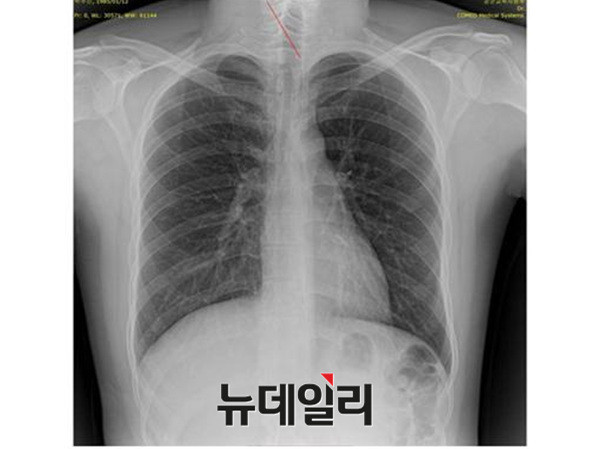

- ▲ 박주신씨 명의의 자생병원 엑스레이. ⓒ 뉴데일리DB

반면 지난해 12월부터 시작된 양승오 박사 등 시민 7명에 대한 공직선거법 위한 공판을 통해 새롭게 밝혀진, 박주신씨의 ‘공군훈련소 입소 당시 엑스레이’(촬영일자 2011년 8월 30일, 이하 공군 엑스레이)와, 주신씨가 ‘비자발급을 위해 촬영한 세브란스병원 엑스레이’(촬영일자 2014년 7월 31일, 이하 비자발급용 엑스레이)는 각각 박주신씨 본인의 신체를 촬영한 것으로 받아들여지고 있다.

이들 3개의 엑스레이는 모두 박주신씨의 신체를 촬영한 것으로 알려져 있기 때문에, 이들 엑스레이에 대한 판독결과 피사체를 동일인으로 볼 수 없는 유의미한 차이점이 발견된다면, 이는 박주신씨의 대리신검 혹은 영상자료 바꿔치기 의혹을 뒷받침하는 결정적 단서가 된다.

세계적 권위를 인정받은 영상의학 전문의인 양승오 박사(동남권원자력의학원 암센터 핵의학과 주임과장)와 치과의사 김우현씨 등 박주신씨 병역비리 의혹을 주장해 온 시민들은, 위에서 언급한 세 개의 엑스레이에 대한 비교 판독 결과, 이들 엑스레이를 같은 사람의 것으로 볼 수 없는 차이점을 발견하고 이를 재판부에 증거자료로 제출했다.

박주신씨의 자생병원 X-Ray를 보면, 오른쪽 제1 늑골부위에 ‘석회화’ 현상이 나타난다. 그러나 주신씨가 공군 입대 당시 찍은 X-Ray에는 이런 모습이 전혀 보이지 않는다.

이런 차이에 대해 양승오 박사의 변호인인 차기환 변호사 등은 "각각의 X-Ray를 찍은 사람이 동일인이 아니라는 것을 입증한다"고 설명했다.